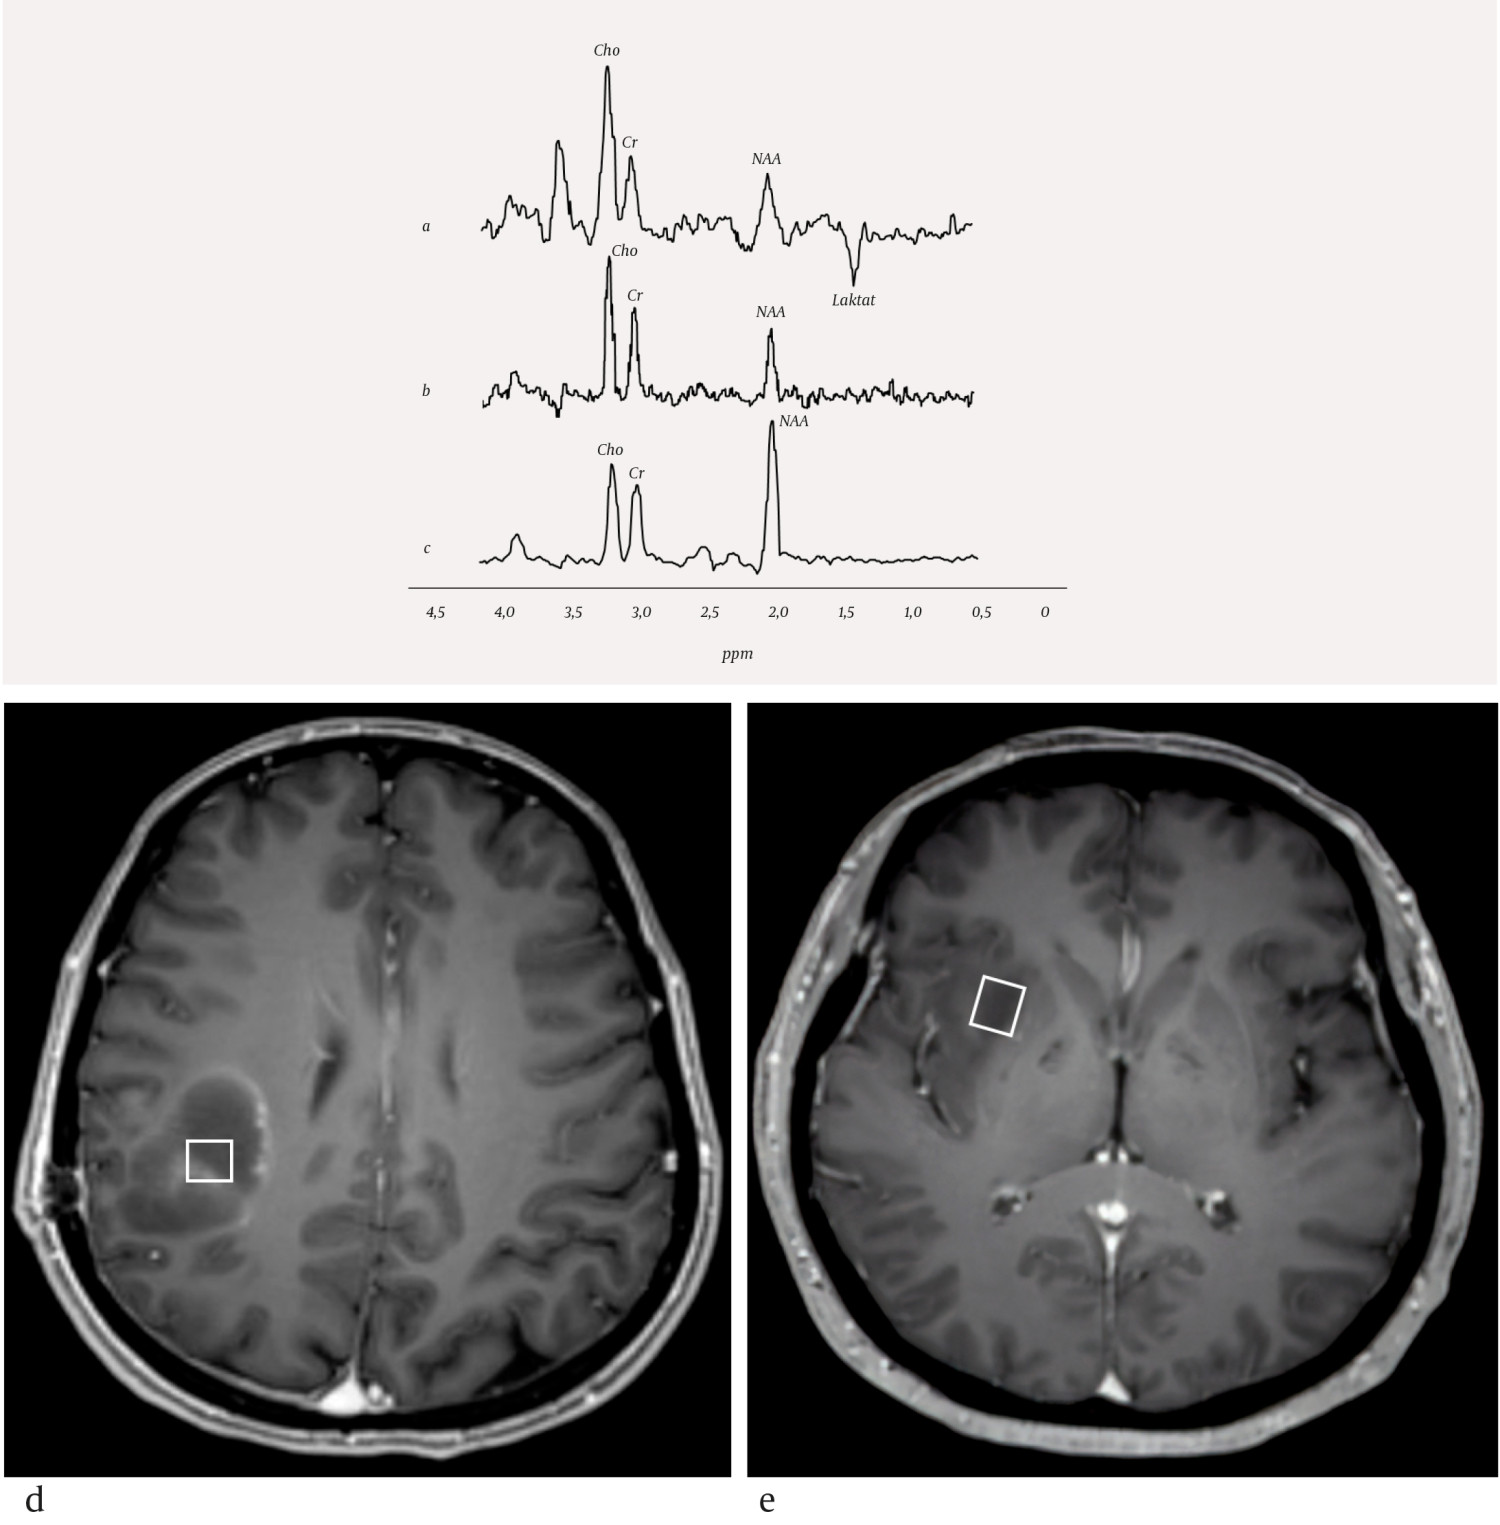

Nevrometabolske sykdommer utgjør en stor og heterogen gruppe medfødte tilstander. Insidens for disse tilstandene enkeltvis er svært lav, mens samlet insidens er estimert til å være 1 per 800–2 500 fødsler (3, 4). De fleste pasienter med nevrometabolsk sykdom har forsinket utvikling eller nevrologiske symptomer og tegn som nyfødt eller i tidlig barnealder. Unntaksvis kan nevrometabolske sykdommer også debutere i voksen alder. Mange nevrometabolske sykdommer gir uspesifikke strukturelle forandringer i sentralnervesystemet som kan karakteriseres med MR-avbildning, men det kan være vanskelig å stille en sikker diagnose kun fra bildefunn. For enkelte nevrometabolske tilstander kan derfor MR-spektroskopi være nyttig på grunn av evnen til å beskrive hjernevevets sammensetning av metabolitter. Noen få sykdommer har en helt sykdomsspesifikk profil ved MR-spektroskopi (5), mens andre har en MR-spektroskopi-profil som kombinert med bildefunn og resultater av kliniske undersøkelser er spesifikk for tilstanden (2). Vanlige endringer i patologiske MR-spektre er redusert mengde N-acetylaspartat, redusert eller økt mengde kolin, økt mengde myo-inositol og tilstedeværelse av laktat. Eksempler på nevrometabolske sykdommer som MR-spektroskopi kan bidra til å karakterisere, er mitokondrielle sykdommer og enzymatiske defekter (figur 1a og 1b).

Enzymatiske defekter kan medføre svikt i cellulære prosesser dersom et spesifikt enzym mangler eller er defekt. Alvorlighetsgrad avhenger av hvilket enzym som er defekt, og det kliniske bildet ved sykdommer i denne gruppen er høyst varierende. Canavans sykdom er en leukodystrofi, hvor hvit substans blir ødematøs, og det dannes væskefylte hulrom (figur 1d). Pasienter med Canavans sykdom har spesifikke genmutasjoner som medfører mangel på enzymet aspartoacylase, som er essensielt for spalting av N-acetylaspartat til aspartat og acetat. Enzymmangelen medfører opphoping av N-acetylaspartat i hjernen og hindret syntese av myelin. Den vanligste formen av sykdommen opptrer ved seks måneders alder og gir omfattende svikt i nevrologiske funksjoner (6). Sykdomstegn er irritabilitet, hypotoni og dårlig overkroppskontroll. Sykdommen medfører sterkt redusert utvikling hos barnet, og kan gi økt hodeomkrets, dårlig øyemotorikk, blindhet, epilepsi, muskelstivhet og spasmer. Forventet levetid er omkring ti år. MR-spektroskopi av pasienter med Canavans sykdom viser sterkt forhøyet signal fra N-acetylaspartat (figur 1b). Canavans sykdom er eneste kjente metabolske sykdom som medfører en økning i mengde av N-acetylaspartat.

Mitokondriesykdommer er en heterogen sykdomsgruppe som gir progressiv eller intermitterende hjerneskade (7). MR-avbildning viser varierende funn med ødem og vevsdestruksjon, men bilateral affeksjon av basalgangliene er typisk. Sammen med MR-avbildning og kliniske funn kan MR-spektroskopi bidra til å identifisere og karakterisere mitokondrielle sykdommer. Det mest gjennomgående funnet ved MR-spektroskopi er tilstedeværelse av laktat på grunn av endret intracellulær energiproduksjon, ofte fulgt av redusert N-acetylaspartat, som indikerer celletap. Leighs syndrom er en mitokondriopati som kan gi utviklingsforsinkelse, spastisitet og hjernestammedysfunksjon. MR-avbildning viser typisk symmetriske signalforandringer i basalgangliene, thalamus og hjernestammen. Laktat i MR-spektre fra disse områdene styrker mistanken om Leighs syndrom (figur 1a).